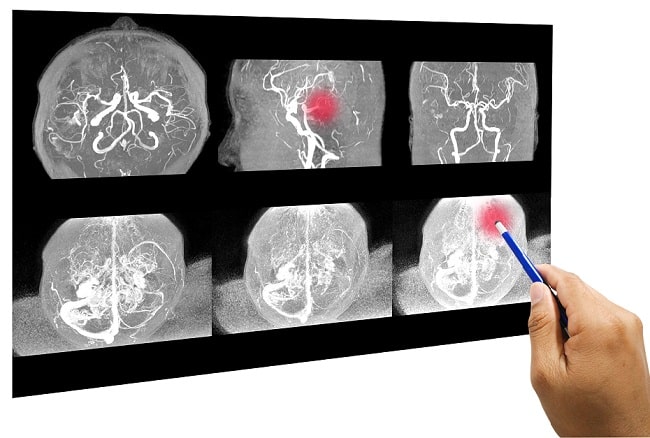

Pemeriksaan Medis untuk Stroke Iskemik Akut

Setelah gejala muncul, pasien perlu segera dibawa ke rumah sakit. Dokter biasanya melakukan beberapa pemeriksaan, antara lain:

CT Scan atau MRI untuk melihat lokasi dan tingkat kerusakan otak

Perkembangan teknologi medis membantu deteksi dan pengobatan stroke lebih cepat. CT Scan, MRI, serta software analisis otak memungkinkan diagnosis lebih akurat. Teknologi telemedicine juga memungkinkan konsultasi dokter spesialis secara cepat, terutama di daerah yang sulit dijangkau.